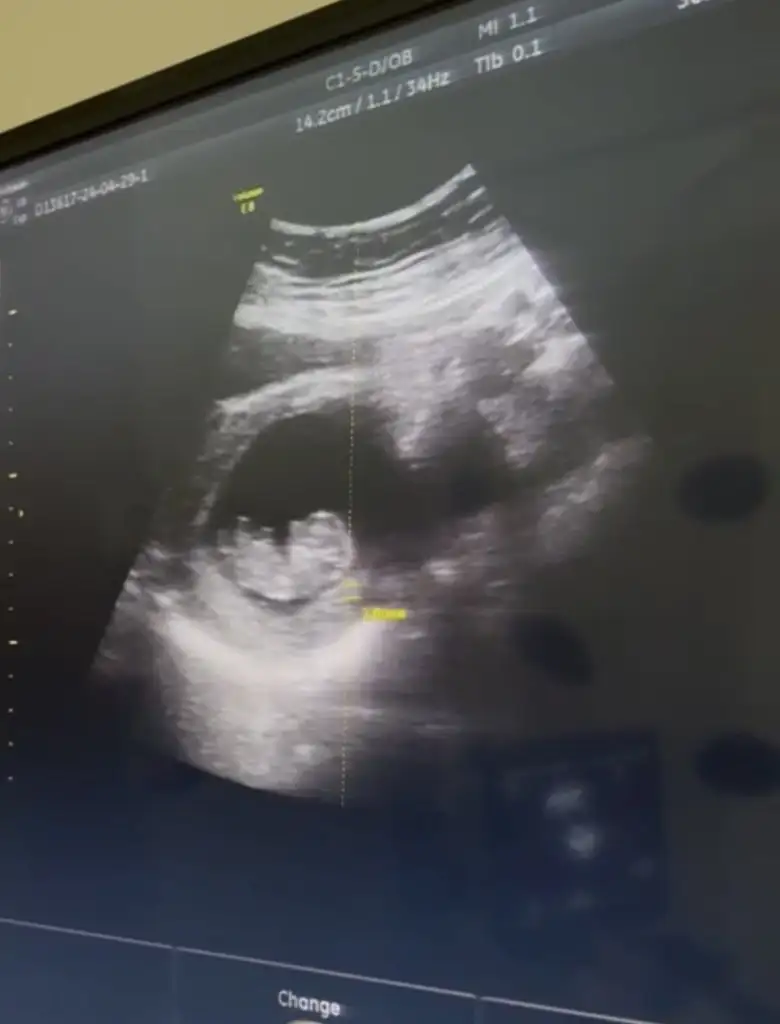

Neden kimse bana tahminde bulunmadıCinsiyet tahmini yaparmısınız 11haftalık

Tamamen hissiyatıma göre söylüyorum kız gibi geldi bana12 haftalık bizede bakar mısınız